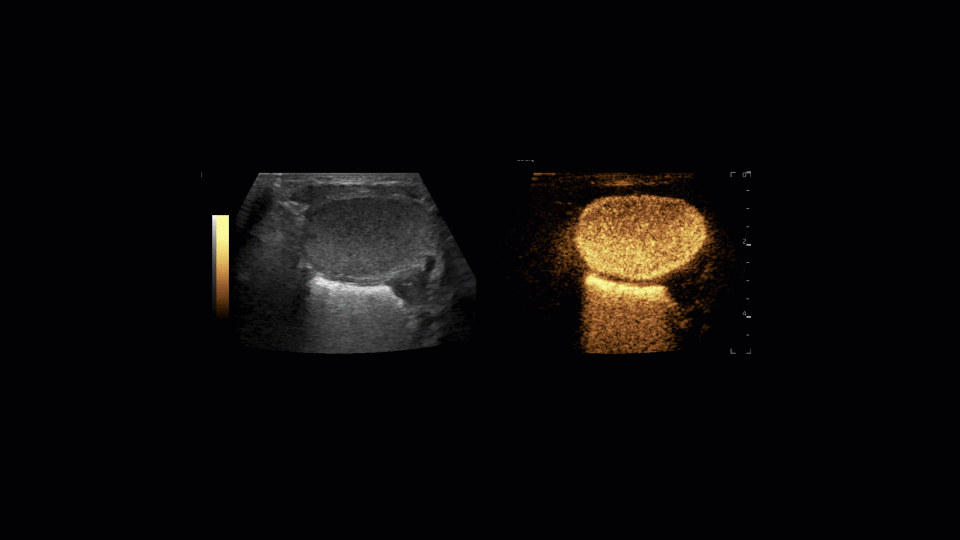

ceVUS is used to diagnose vesicoureteral reflux (VUR), a condition where urine flows backward from the bladder to the kidneys. VUR can increase the risk of infections and scarring. This new procedure has the potential for other applications as well. It can help identify kidney abnormalities, anatomical variations, and guide treatment decisions. Replacing fluoroscopy and X-rays, ceVUS uses tiny micro bubbles in its contrast agent, which catch the ultrasound waves to make the signal show if any urine backflow occurs.

The new ultrasound-based procedure has many advantages over the methods currently in use at other institutions. Unlike X-ray imaging, ceVUS avoids exposing children to radiation and it allows children to sit in a potty chair or stand, making it less stressful than lying flat on a table in a medical setting that some children experience as claustrophobic. ceVUS can provide continuous real-time visualization of the urinary system during the exam, increasing the diagnostic utility. And studies show that ceVUS is just as effective as traditional X-ray methods in diagnosing VUR.

Courtier described the second procedure at Mission Bay, performed on July 1, 2024, “We got excellent visualization of the kidneys and bladder, all without ionizing radiation. Our sonographer Jennifer Paoletti was key in helping to coordinate all of the supplies and worked in conjunction with our Mission Bay nursing team.”